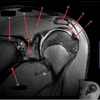

1

What is letter A?

SUPRASPINATUS TENDON

Q

A

3

CORACOID PROCESS

4

What is letter B?

5

What is letter C?

6

What is letter D?

7

8

9

10

11

12

13

15

TERES MINIR MUSCLE

16

INFRASPINATUS MUSCLE

17

ACROMION

18

DELTOID MUSCLE

19

SPINE OF SCAPULA

20

21

INFRASPINATUS TENDON

22

25

SUPRASPINATUS MUSCLE

26

27

What is letter E?

28

GREATER TUBEROSITY

29

What is letter G

SCAPULA